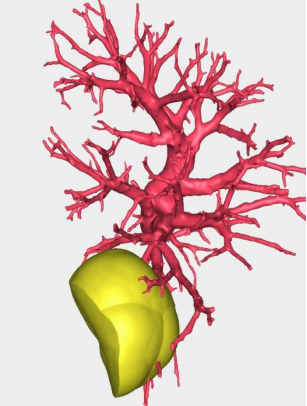

接诊的胸外科主任黄永高认真查看了老李的影像资料:病灶在右下肺后外基底段(S9+S10),直径约2cm,毛玻璃成分为主。考虑到老李的情况,黄主任决定采取右下肺后外基底段切除术,以最大限度地保留患者的肺功能,避免进行整个肺叶的切除。但由于S9+S10段的解剖结构复杂,变异较多,为了确保手术的精准与安全,黄主任决定利用先进的肺小结节AI(人工智能)三维重建技术进行术前规划。

(术前模拟,术前手术规划)

在AI技术的辅助下,胸外科手术团队得以清晰地看到病灶的三维结构,以及周围血管、神经的精确分布。这不仅大大提高了手术的精确度,还使得手术过程更加顺畅,减少了不必要的创伤。

遇到复杂肺段切除病例术前进行AI三维重建,AI三维重建能够精准重建了患者的肺部模型、肺结节三维详细分布图,制定术前规划及手术方案。通过三维重建技术建立肺部模型,明确肺结节的详细位置及与周围动脉静脉、支气管之间的关系,精准规划了手术路径及切除范围,就像开车安装了GPS导航一样,使手术思路特别清晰,能够最大限度地保留患者肺功能,提高手术的安全性、精确性,缩短手术时间,再加上单孔胸腔镜技术,真正实现了胸外技术的“微中再微”。